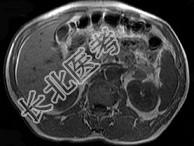

- 单项选择题男,52岁, 下肢无力伴多饮多尿2年余,实验室检查: 低血钾,血醛固酮水平及24小时尿醛固酮定量超过正常值, MRI检查如图所示,应诊断为 ( )

A、左肾上腺囊肿

B、左肾上腺腺瘤

C、左肾上腺嗜铬细胞瘤

D、左肾上腺髓脂瘤

E、左肾上腺转移瘤